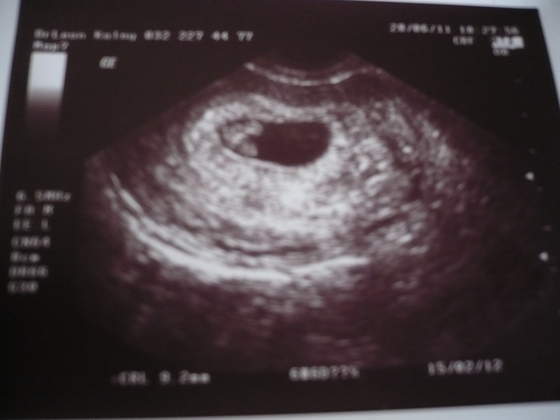

Jestem w wedlug kalendarza w 4tygodniu . Troche jestem zaniepokojona:-(. Moja ostatnia ciaze niestety stracilam w 6 tyg. wtedy strasznie nie bolaly piersi,a przy tej od poczatku bolaly jak na @ ,a od wczoraj bol piersi ustepuje...i znowu ten strach przed strata naszej fasolki...